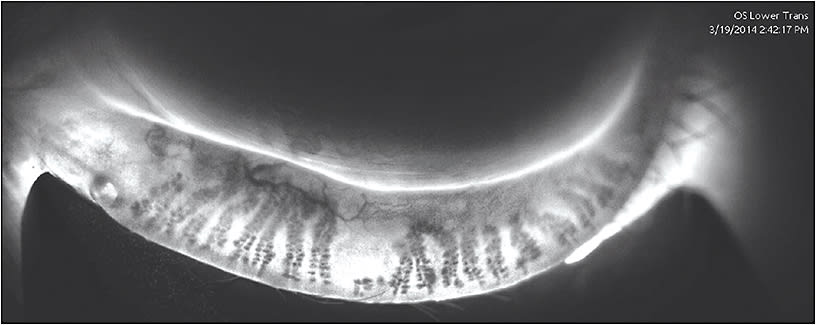

In addition, the routine use of LipiScan has been a fundamental change in our practice. We automatically scan every patient, looking for gland atrophy and structural changes to the meibomian glands, rather than waiting for patients to report symptoms. I can predict potential problems for patients with LipiScan and it is a great educational tool.

When using the LipiScan with Dynamic Meibomian Imaging, I can evaluate the anatomy. If a patient has lost 50% of his meibomian glands, I tell him, “We need to maintain the remaining 50% for the rest of your life to avoid discomfort, poor vision, and potentially significant pathology.”

Dr. Epstein: I see many patients on referral, and I tend to spend more time with them because their disease is usually advanced. To me, meibography is worth its weight in gold. I have become quite the aficionado in using this technology and can explain it to patients. I think it really reinforces that they can be helped because they have a problem that is visible and discernible, and that they can understand. Point-of-care testing is certainly helpful. If I had to choose only one, it would definitely be LipiScan.